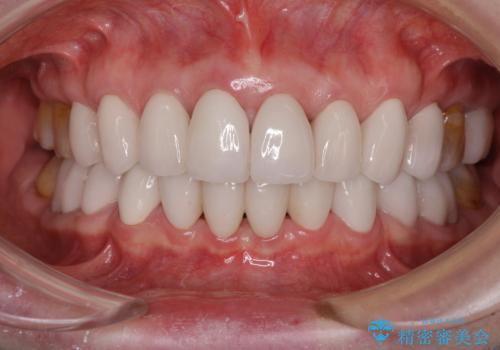

出っ歯を改善した後に真っ白な歯に 矯正歯科治療と審美歯科治療